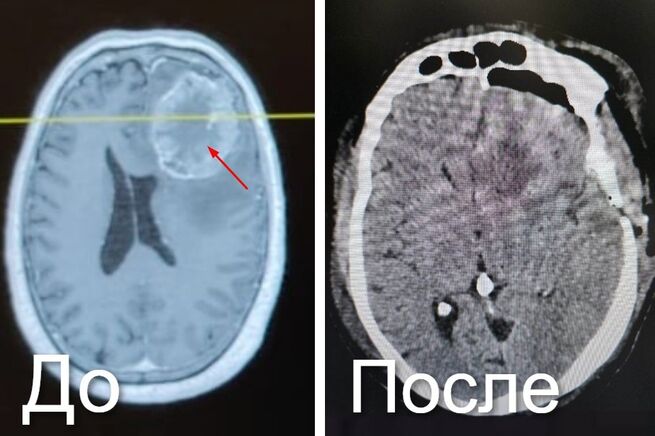

Как рассказал министр здравоохранения Кузбасса Андрей Тарасов, новообразование возникло как метастаз рака прямой кишки, перенесенного в 2019 году. Оказалось, что все эти годы кузбассовец не наблюдался у онкологов. В результате опухоль достигла размера 7,5х6 см, спровоцировала сильную боль, тошноту и потерю координации.

– Опухоль имела нечеткие границы и обильное кровоснабжение. Чтобы полностью удалить ее, специалисты использовали хирургический микроскоп и нейронавигационную систему, – рассказал Андрей Тарасов.

Уточняется, что операция длилась 5,5 часов.

Известно, что пациент достаточно быстро восстановился. Неврологического дефицита не возникло.